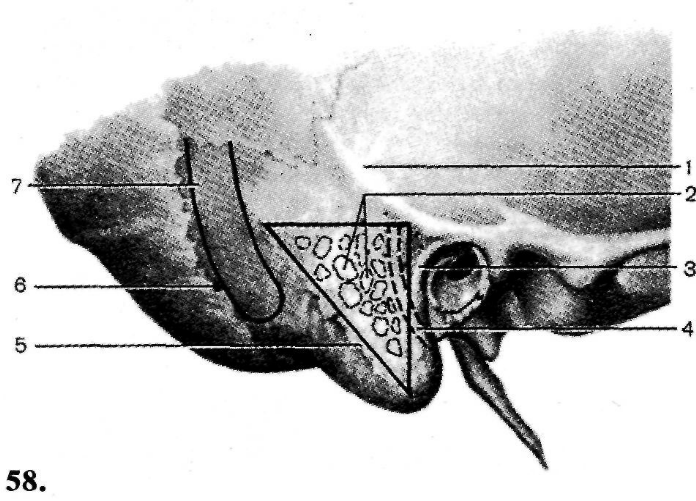

Анатомия сосцевидного отростка